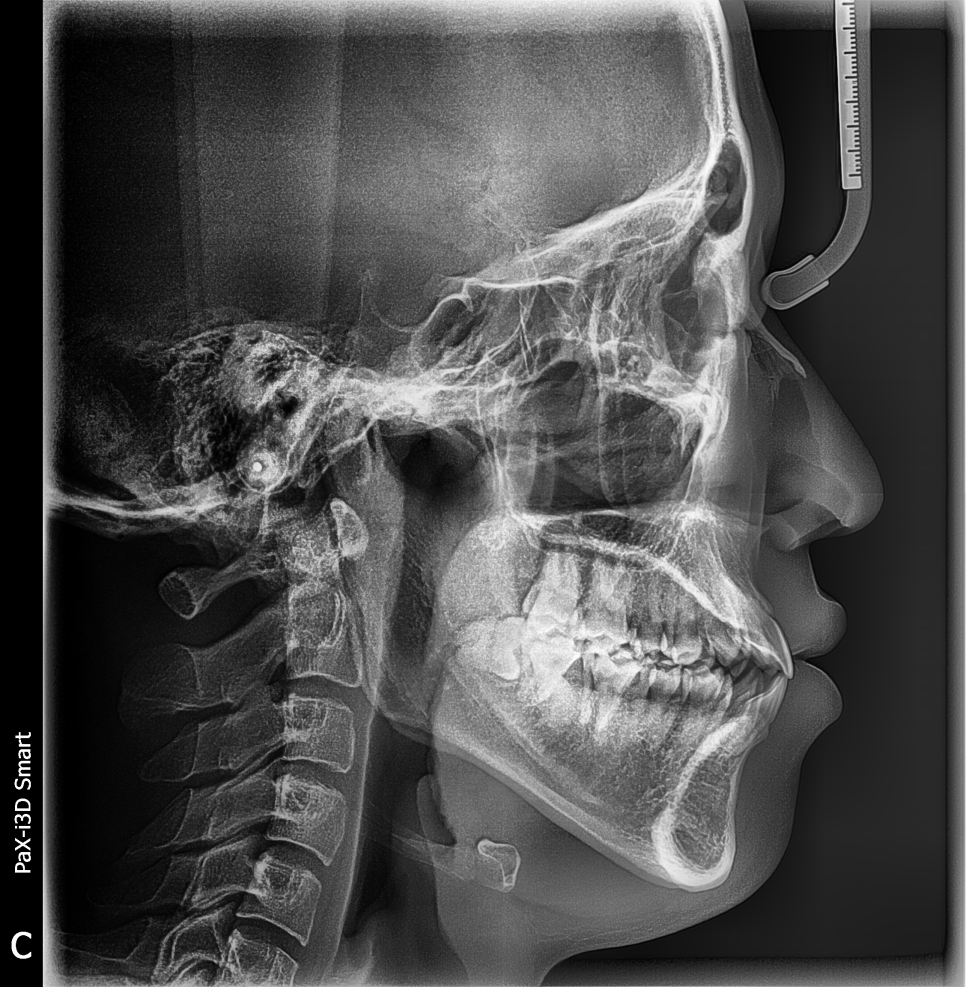

최대리님은 전체교정 시작하신지 13개월째세요.

![강남역치과 [투디치과] 최대리님 교정진행중/직원들도 믿고 교정해요! 관련 이미지 1](https://pub-9f2bb3498faf4d1d8714b41df24753e3.r2.dev/content/clinics/archive/grb36g4zmx/naver_blog/dental2d/assets/by_hash/7356a0ce54118eac372c8ca9f45c05b9edc784ef759c9c8d89b183fa259bdee5.png)

투디치과 최대리님 교정전

최대리님 교정전 사진이에요. 잘 보시면 입술이 좀 나와 보이죠?

절대 위 이모티콘처럼 입술을 내밀고 찍지 않으셨어요ㅋㅋㅋㅋㅋㅋ 이날 컨디션도 최상이셔서 뾰루퉁하시지도 않았어요!